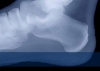

AYAKTA GUT HASTALIĞI Kanda ürik asit fazlalığı çağdaş toplumlarda çok kişinin sorunu olma yolundadır. Protein ağırlıklı beslenen ve obes olma sınırına yaklaşan bu kişilerde kandaki bu madde bir süre sonra eklemlere birikmeye başlar. İşte bu dönemde artık gut hastalığı başlamıştır.

Hastalık sadece eklemlerde olmaz. Kulak kepçesinde bile ürik asit kristalleri birikebilmektedir. Zamanla özellikle ellerde öyle ciddi deformasyonlar oluşabilir ki kişinin ellerini kullanması imkansız hale gelebilir.